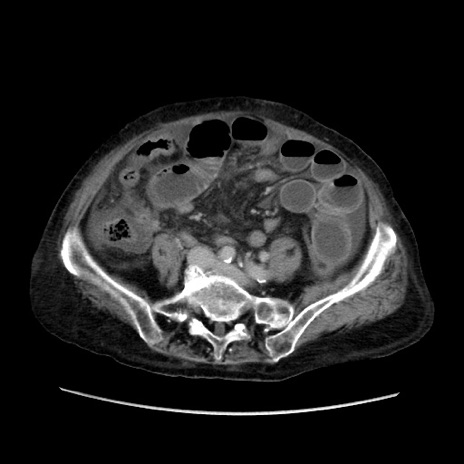

症例31(横断像)

【症例】80歳代 女性

【主訴】腹部膨満感

【現病歴】他院にて肝硬変にてフォロー中。1週間前から便秘、腹部膨満感、臍部腫瘤あり受診となる。

【既往歴】肝硬変

【身体所見】腹部膨隆あり、皮膚変化なし、疼痛なし。

【データ】WBC 4600、CRP 0.25